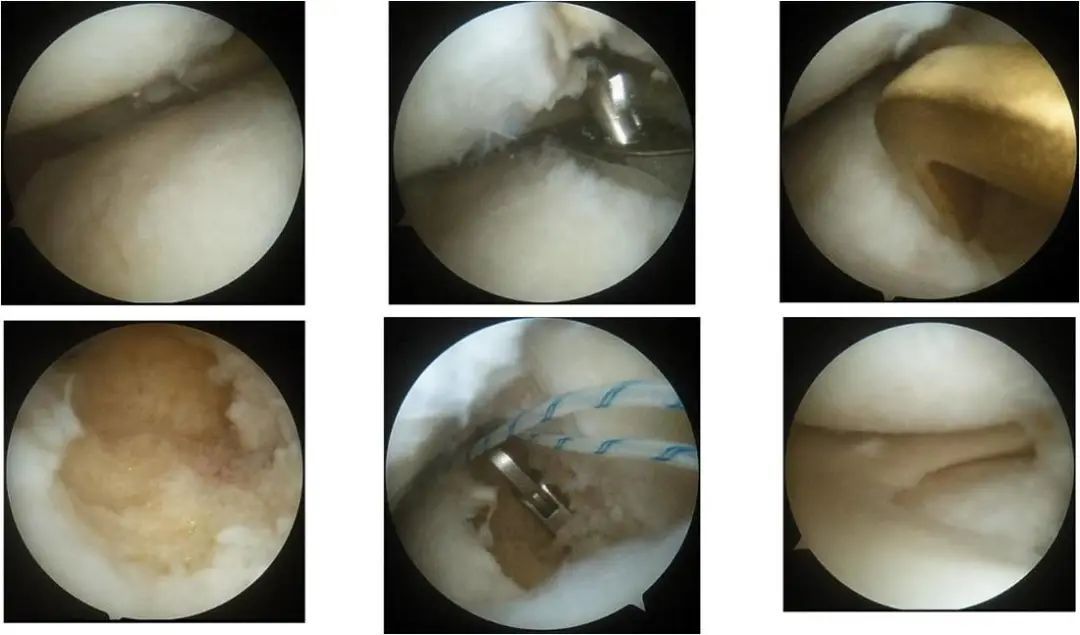

所移植的半月板假体

引入同种异体半月板,缝合器固定,镜下显示移植物与受体匹配良好